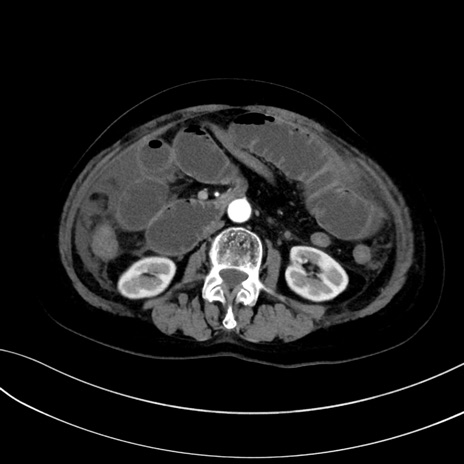

症例13 CT(横断像)1日半後